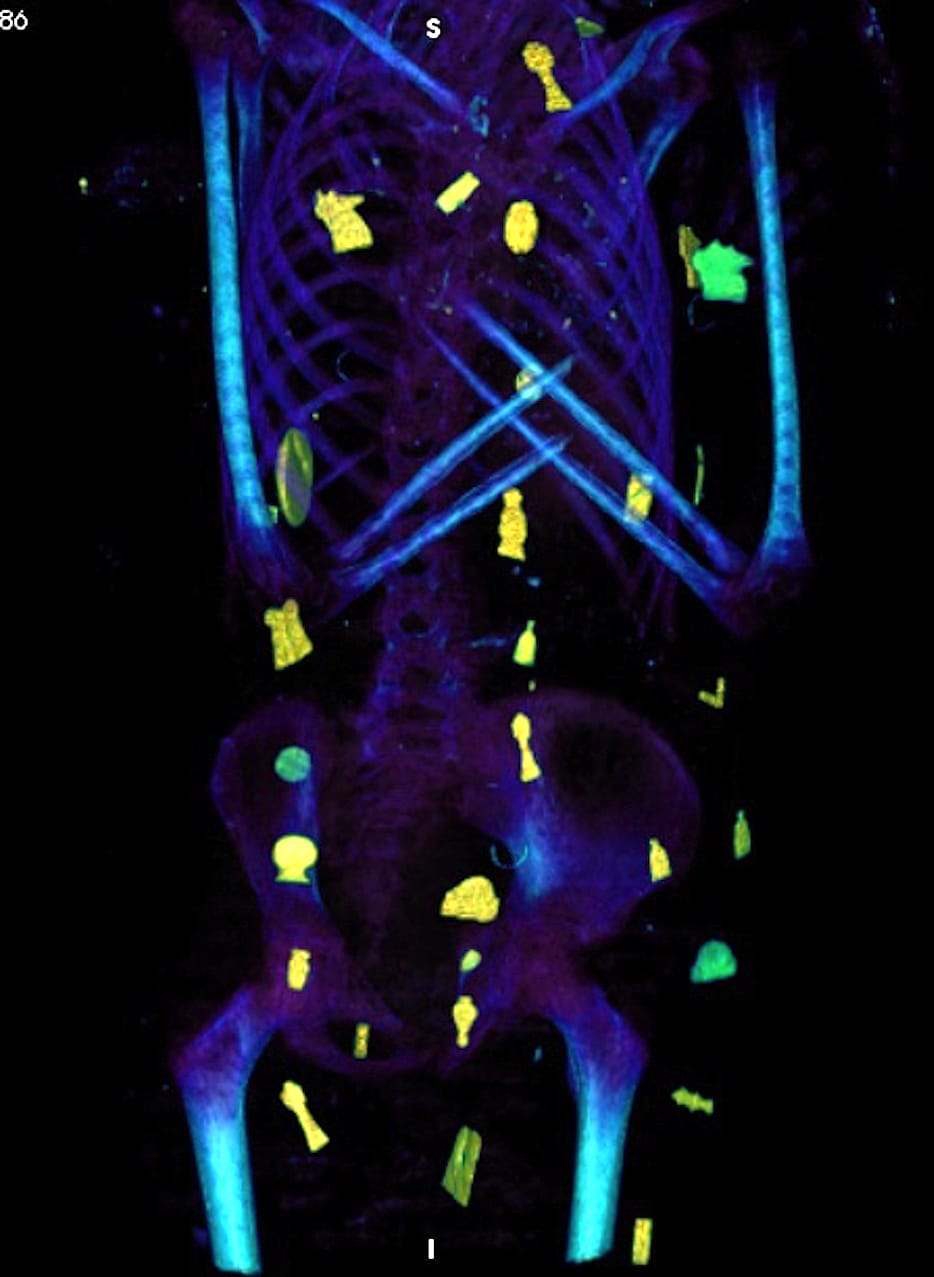

كما أوضحت صور الأشعات المقطعية الثنائية والثلاثية الأبعاد عن وجود حوالي 49 تميمة مرتبة ترتيبًا منمقًا في ثلاث أعمدة بين طيات اللفائف الكتانية وبداخل تجويف المومياء. كما أظهرت الأشعة أيضا 21 شكلًا مختلفًا للتمائم مثل عين المعبود حورس والجعران وتميمة الأفق والمشيمة وعقدة إيزيس والريشتان، وغيرهم.

ومن خلال نتائج قياسات الأشعة تبين أن 30 تميمة من التمائم المكتشفة داخل المومياء صنعت من الذهب بينما باقي التمائم صنعت من الأحجار أو الفيانس، بالإضافة إلى تميمة علي شكل لسان من الذهب وضعت بداخل فم المتوفي ليتمكن من التكلم في العالم الآخر، كما يوجد تميمة على شكل أصبعين أسفل الجذع لحماية فتحة التحنيط، وتميمة أخرى كبيرة من الذهب لجعران القلب موجودة بداخل تجويف صدر المومياء، والذي تم عمل مستنسخ منه باستخدام الطباعة ثلاثية الأبعاد.

وأشارت صباح عبدالرازق مديرة المتحف المصري بالتحرير، الدراسة على تقدير قدماء المصريين للأطفال، حيث تمتعت هذه المومياء بطقوس جنائزية مميزة تمكنها من البعث والحياة الأخرى حسب معتقدات المصريين القدماء، بالإضافة إلى إظهار المكانة الاجتماعية الرفيعة لصاحب المومياء فهو صبي حظي بطقوس جنائزية عالية المقام، إلى جانب حالته الصحية الجيدة حيث أنه كان يتمتع بأسنان وعظام سليمة وبلا علامات تدل علي أمراض أو أعراض سوء تغذية.